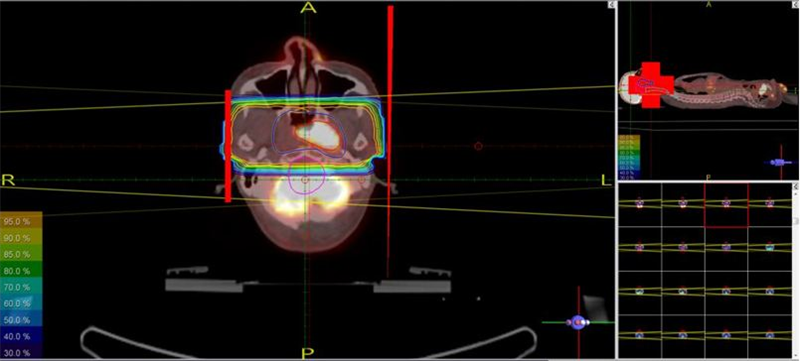

* Sau khi chụp, toàn bộ hình ảnh mô phỏng sẽ được chuyển sang hệ máy tính lập kế hoạch điều trị -TPS qua cổng DICOM. Các bác sỹ xạ trị xác định các thể tích xạ trị: GTV (thể tích khối u thô) trên hình CT mô phỏng, CTV (thể tích bia lâm sàng) và PTV (thể tích lập kế hoạch xạ trị). Trên hình PET/CT mô phỏng sẽ xác định được BTV (thể tích khối u sinh học) và các cơ quan cần bảo vệ (hình 3).

Trên hình CT mô phỏng xác định được:

-         GTV (màu vàng)

-         CTV (màu xanh lá cây)

-         PTV (màu đỏ)

Trên hình PET/CT mô phỏng xác định được:

-         BTV (màu vàng)

Hình 3: Các thể tích xạ trị được vẽ trên hình CT và PET/CT mô phỏng.

Hình 5: Đặt các trường chiếu, các segments trong kế hoạch xạ trị 3D

Hình 6: Đặt các trường chiếu, segments và tính liều trong kế hoạch xạ trị IMRT.